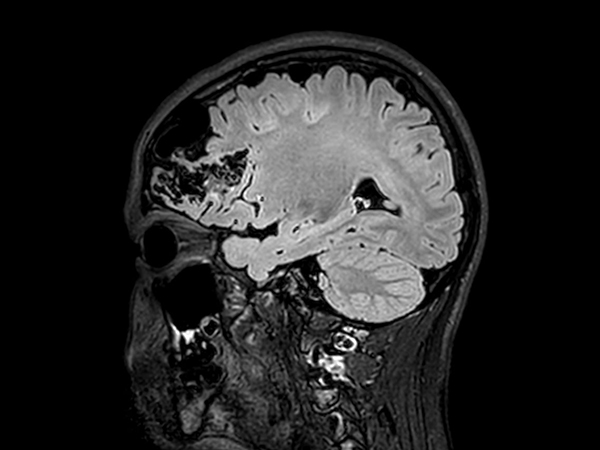

Pediatric brain with AVM

Pediatric patient with frontal brain AVM. MultiVane XD is used to achieve high resolution diagnostic images, even in the case of severe patient motion. SWIp sequence is added to acquire exquisite susceptibility contrast. The 3D sequences with isotropic voxel size enable reformats in any plane without loss of resolution. And 4D-TRAK XD, a fast, dynamic contrast-enhanced MR Angiography method allows to achieve high spatial and temporal resolution simultaneously. Integration of Compressed SENSE acceleration technique enables speeding up of the entire exam.

Sagittal 3D T2w FLAIRCompressed SENSE